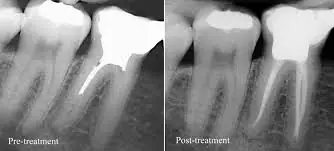

At Doctors Clinic Diagnostic Center in Dubai Healthcare City, our oral surgeons focus on safe, pain managed wisdom teeth extractions. whether erupted or impacted. We use OPG/CBCT imaging for precise planning, effective local anesthesia, and sedation options when needed to keep you comfortable.

Impacted teeth seen on X-ray/CBCT or crowding risk

Oral surgeons experienced in impacted, complex, and nerve-proximity extractions with CBCT guided planning.